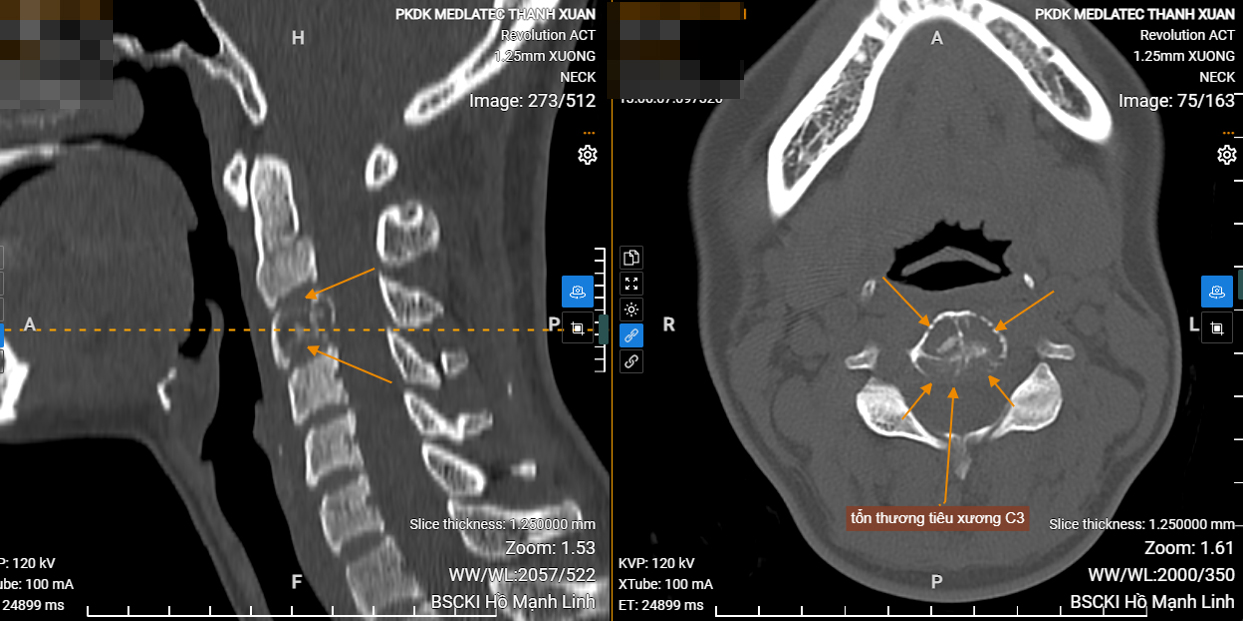

Bác sĩ CKI. Kiều Trí Lộc - Chuyên khoa Chẩn đoán hình ảnh tại Hệ thống Y tế Medlatec cho hay, sau khi thăm khám lâm sàng và phát hiện các dấu hiệu bất thường tại cột sống cổ, bệnh nhân L được chỉ định chụp cắt lớp vi tính để đánh giá chi tiết hơn. Kết quả cho thấy tổn thương tiêu xương tại thân đốt sống C3, nghi ngờ là u xương thứ phát.

Bệnh nhân tiếp tục được chỉ định chụp MRI bổ sung để làm rõ chẩn đoán. Kết quả MRI ghi nhận hình ảnh tổn thương gây xẹp thân đốt C3, theo dõi di căn.

Dựa trên cơ sở kết quả cận lâm sàng đã thực hiện, bác sĩ chẩn đoán bệnh nhân mắc ung thư vú di căn xương đốt sống cổ C3. Bệnh nhân được chuyển đến Bệnh viện Trung ương Quân đội 108 để điều trị.